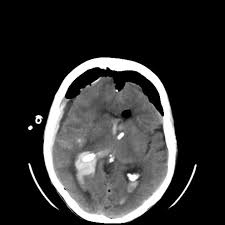

Computed tomography ct scan revealed symmetrical ventricular dilatation. Ported as a very common cause of shunt dysfunction 5 5. After placement of vp shunt the air introduced to the brain and the patient developed tension pneumocephalus which is neurosurgical emergency.

3 the purpose of ventriculoperitoneal shunt vps surgery is to allow csf flow through a shunting mechanism from the intracranial ventricles to the peritoneum. Ct brain revealed pneumoventricle and extensive subdural pneumocephalus overlying bilateral frontal lobes causing compression of the frontal lobes and separation of their tips characteristic of the mount fuji sign fig. In 126 frontal approach 48 malfunction and obstruction with shunt revi sion were seen.